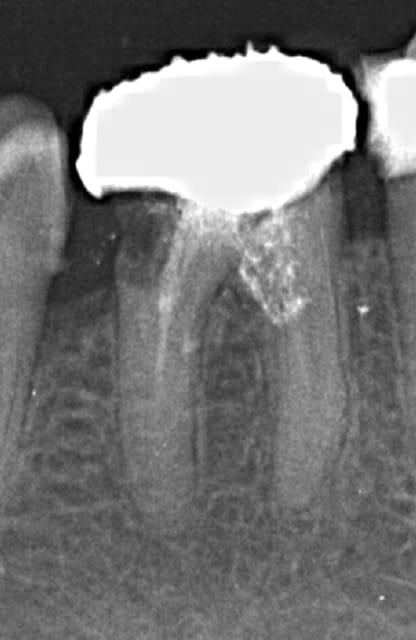

Je m'entraine au mac spaden mais abrès avoir réalisé des bouchons apicaux au friendo ( enfin j'essaye par ce que ca bloque un peu trop loin de l'apex vu que je n'ai pas toutes les tailles d'inserts lol !); Pas franchement de meilleure image qu'au monocone scellé.

Je me fais chier pour rien je pense mais j'appréhende cet engin qui tourne à 40 000 tours ( j'utilise le diametre 40 pour une préparation au R25)

Ca compacte dur par contre vu que l'intégralité du cone ( ici un diametre 40) disparait dans le canal.

En termo-compaction pure à combien de mm de l'apex faut il envoyer l'engin ? vu la pression que ca développe une connerie est vite arrivée.

pas cool de commencer par une 36 de 4 canaux. Par contre.)))))))

R1 iqqn0y - Eugenol

R2 sxl3pa - Eugenol

R3 ulnhut - Eugenol

R4 hefdnh - Eugenol

Loop trrma6 - Eugenol

En thermocompaction faut se tenir à 4mm de l'apex (a peu pres). Et même si on voit pas tout le temps la différence radiologiquement avec le monocone, on est sur que c'est étanche à l'apex (ce qui est pas du tout le cas avec un monocone scellé...)

Oui c'est la meme chose avec le système B utilisé (friendo de hufriedy). Seulement j'ai pas réussi à descendre les inserts à 4 mm de l'apex (trop gros taille FM/06) curieux d'ailleurs dans certains canaux je n'en suis pas loin. Mon obturation est donc en monocone scellé au bout.)))))

Un compacteur de 30. Les revo condensor sont parfait ils ont une bague violette. Je ne me sers presque que de ces thermocompacteurs. La densité des cônes compactes à la radio dépend de leur concentration en eugenol.donc peu significatif. Pour me faire la main je passais le cone puis un.coup de finger spreader et après seulement le compacteur